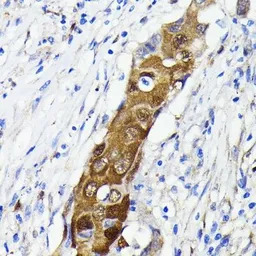

IHC-P analysis of human lung cancer tissue section using GTX00947 NFkB p65 antibody [GT1185].

Dilution : 1:100